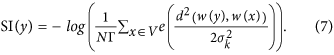

Let w(x) ∈ V to be the viable local representation as a patch that represents pixel x and V indicates all the vessel segments. The average vessel diameter of our dataset is around 5 pixels, so the size of the patch is set as 3 × 3 in this work, where x is the centre of the patch. The patches can be seen as samples of a multivariate probability function (PDF). A number of methods to estimate an unknown multivariate PDF with a sufficient number of samples have been introduced in the literature. The kernel density estimator (KDE) is chosen in this paper. The KDE is appropriate since it is non-parametric, which will allow to estimate any PDF. Therefore, the probability of a patch w(y) can be defined as

where d is a distance function that will be discussed later, K is a kernel, h is a smoothing parameter and N represents the number of pixels. KDE method is capable to blur the contribution of each sample x by spreading it to a certain area in vessel segments with a certain shape46, which is defined by K. The multivariate distribution will have higher probability if the patches are in dense areas. From our experience, the most commonly used and the most appropriate kernel is Gaussian function with zero mean and standard deviation σk. Using a Gaussian kernel, Eq. (5) is rewritten as

The estimated probabilities are taken from an actual PDF by setting a proper constant Γ. σ = 0.2 is chose to substitute h. After determining the probability of the patches, the intensity-based saliency measure can be defined as follows: